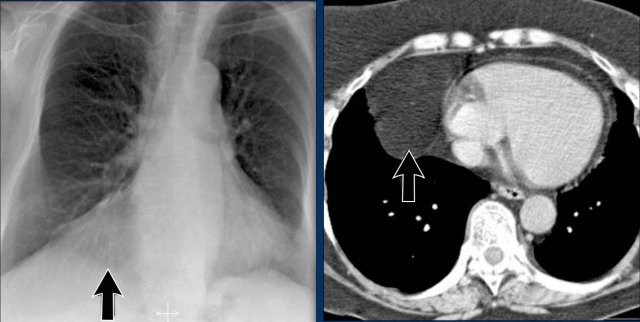

Case Example 3: Valve Replacement & Heart Failure

Post-valve replacement, a patient presents with a markedly enlarged cardiac silhouette on chest X-ray.

Findings

- A large cardiac silhouette

- There is evidence of pulmonary vascular redistribution, suggesting congestive heart failure.

Case Example 3: CT imaging

CT demonstrates a large pericardial effusion.

Tip

Always compare postoperative chest films with preoperative imaging to detect interval changes such as effusions or evolving heart failure.

Pericardial cyst

Pericardial cysts are benign lesions that are anatomically connected to the pericardium and typically contain clear, serous fluid.

The majority of pericardial cysts are located in the anterior cardiophrenic angle, more frequently on the right side.

However, they may also be identified more superiorly, within the pericardial recesses at the level of the proximal ascending aorta and main pulmonary arteries.

Most patients remain asymptomatic.

On chest radiography, a pericardial cyst may mimic an elevated left hemidiaphragm (black arrow).

However, CT more clearly demonstrates a fluid-filled cystic lesion contiguous with the pericardium (yellow arrow).